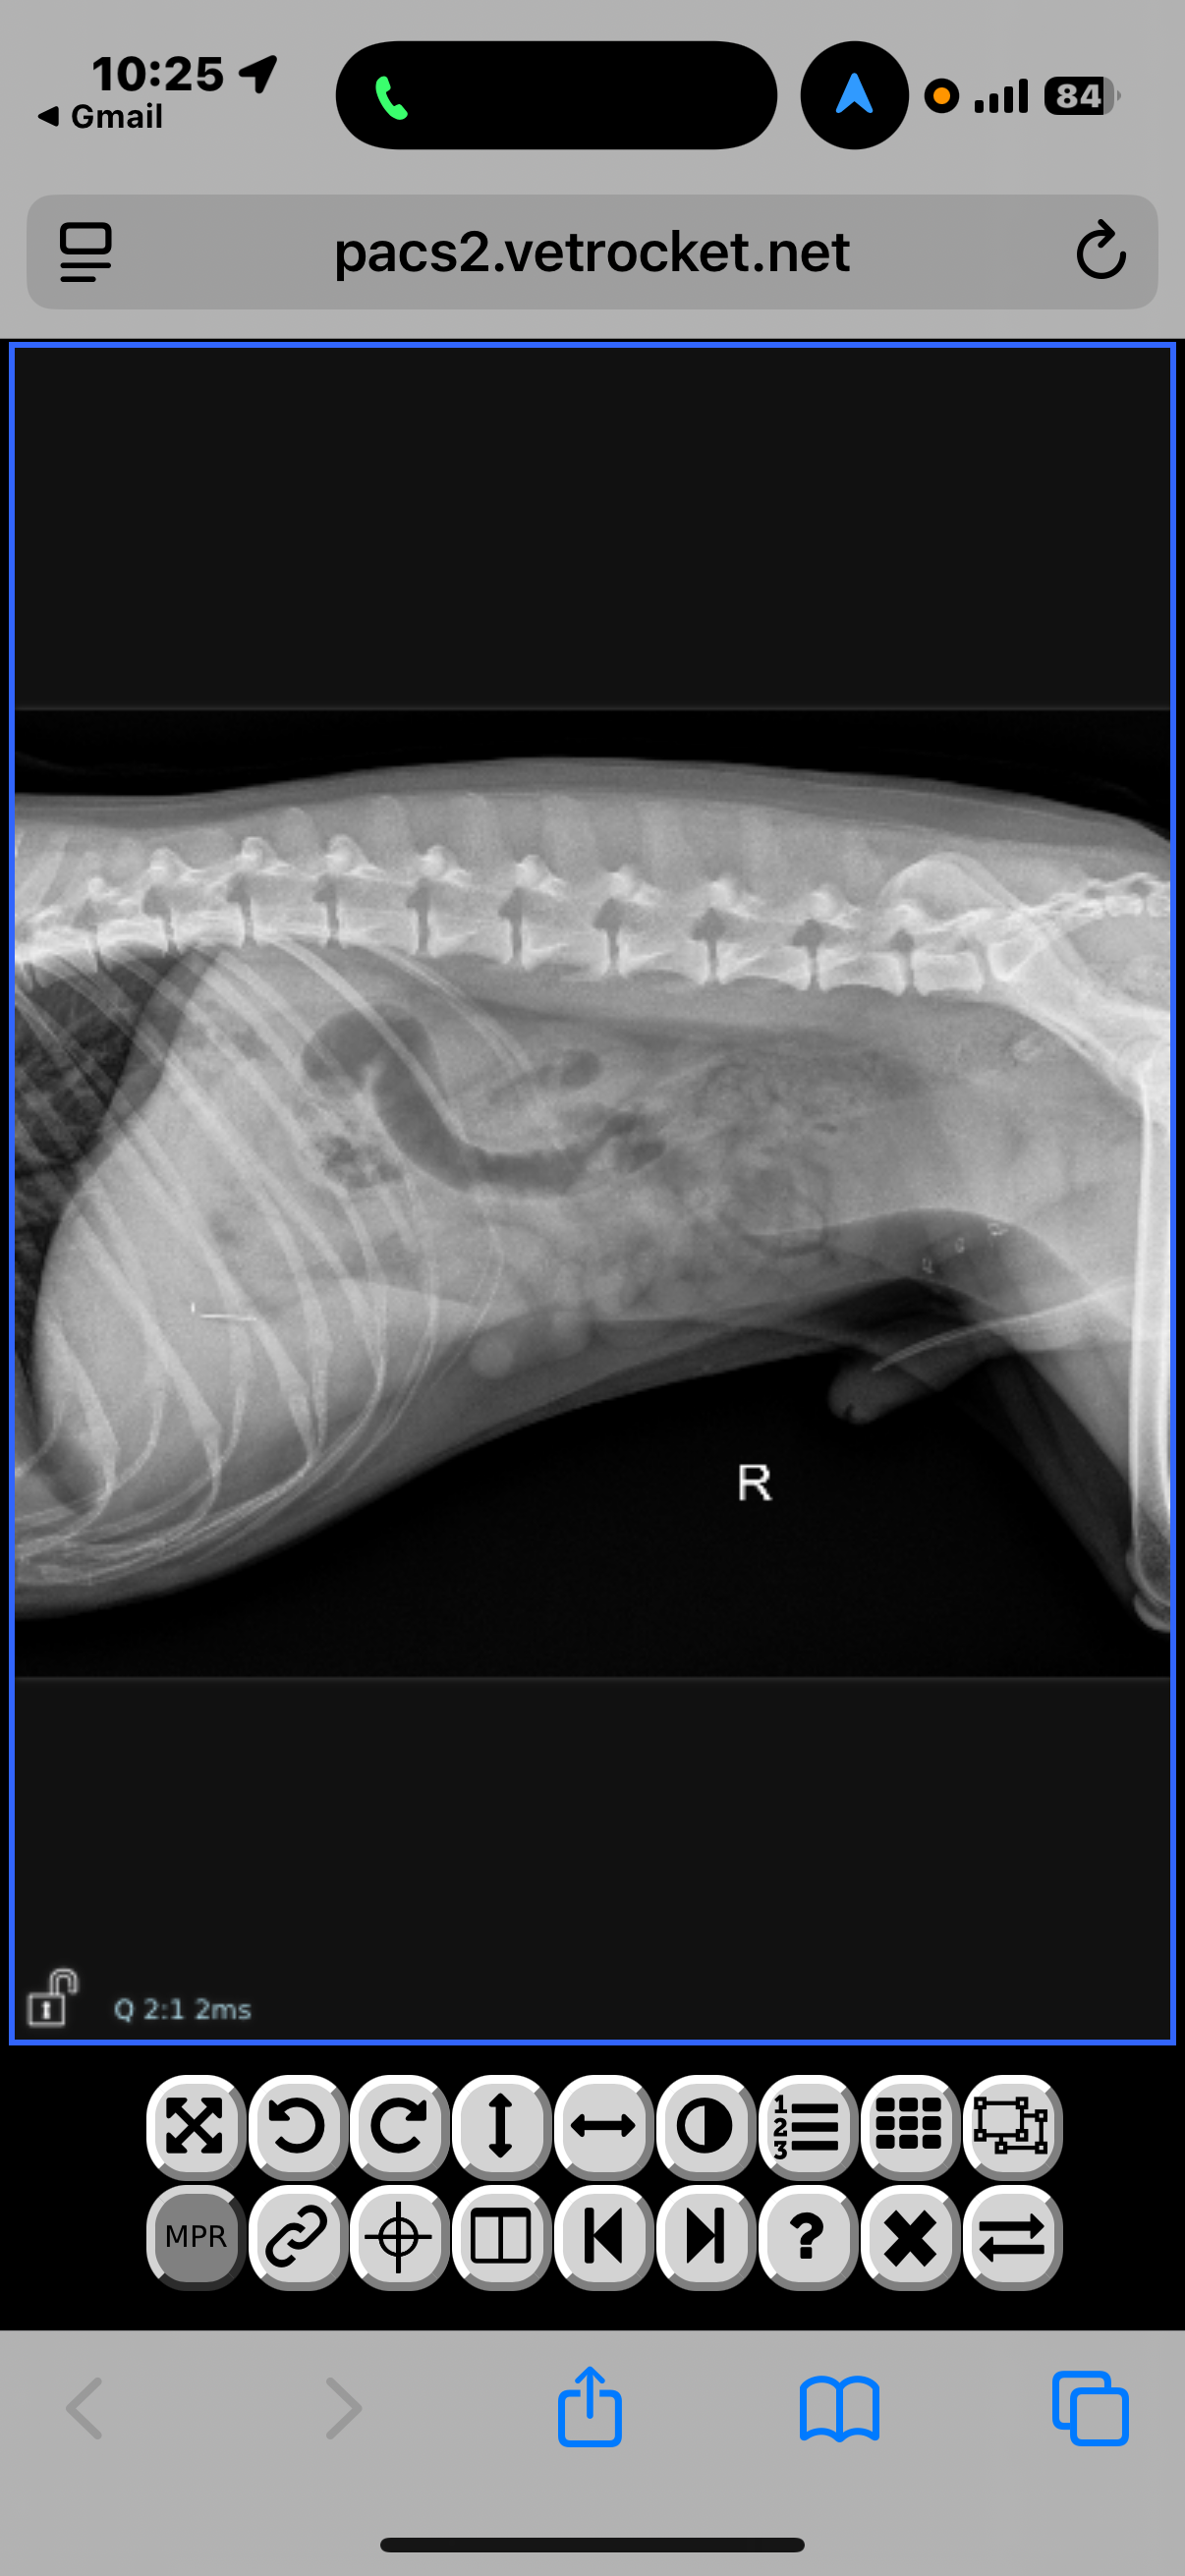

Vegas became seriously ill and required urgent diagnostics, X-rays, and surgery. The total cost from two different specialty animal hospitals came out to over $5,000. I’ve attached all receipts and medical records to show transparency.